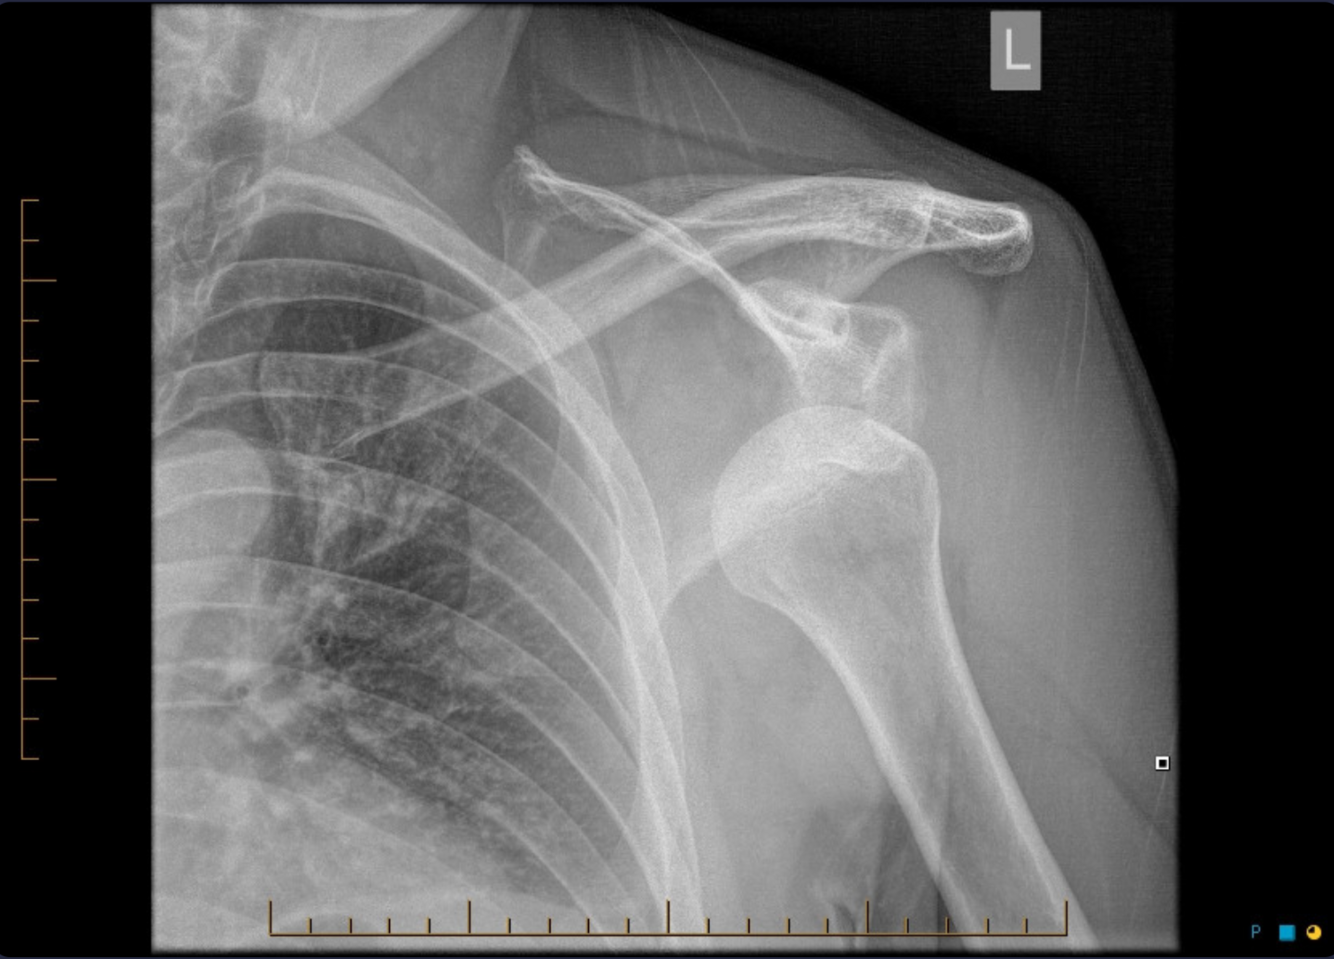

What’s the diagnosis and common lesion associated with this injury?

Dx: Anterior luxation of the shoulder

Lesion: Axilary nerve injury